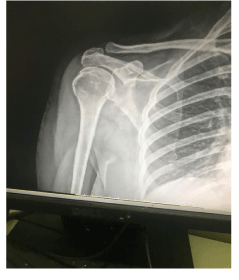

Removing shoulder calcification has already been reported [1], as shown in these two x-rays (Figure 1 and 2). The doctor had expected to have to surgically remove the calcification with all the side effects, pain, time and cost this involves. To see the calcification “disappear on its own” was an exciting mystery. That it was obviously safe encouraged Dr Srinivas at Ravina Hospital [2] in Chennai to tackle another problem that had been impossible.

Figure 1: Shoulder calcification

Figure 2: Shoulder calcification